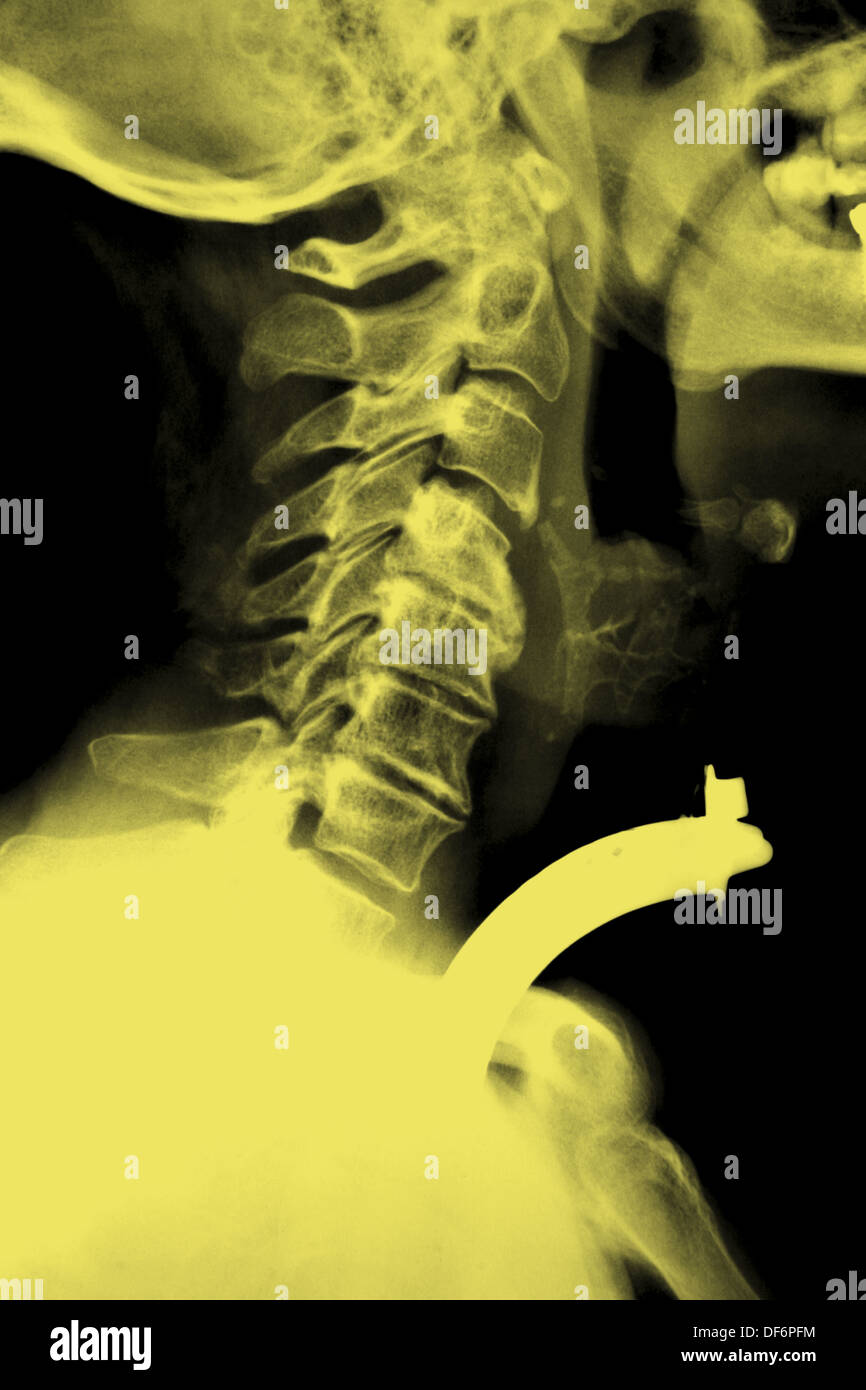

From www.alamy.com

Tracheotomy or tracheostomy. Xrays with tracheal cannula Stock Photo Occluded Trach Indications for emergent tracheostomy include: Tracheostomy is a procedure that creates an opening in the anterior wall of the trachea, through which a tracheostomy tube. To generate sufficient pressure, the tracheostomy must be occluded typically with finger occlusion, speaking valves or capping. A blocked tracheostomy tube is an emergency, and can result in respiratory arrest or death. The inner cannula. Occluded Trach.